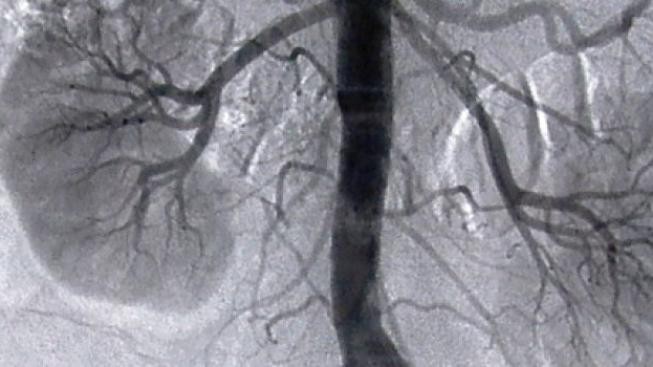

Češi mají v háji ledviny. A neví o tom.

Každý desátý dospělý v ČR má chronické onemocnění ledvin a neví o tom. Ony totiž většinou nebolí a o jejich selhání se třetina pacientů dozví, až kdy mají nastoupit na dialýzu. Tu dostává 6000 pacientů, zhruba 3750 žije s transplantovanou ledvinou. Světový den ledvin si 10. března připomene význam včasného odhalení této nemoci.

"Pacienti léčení pro selhání ledvin na dialýze mají v průměru desetkrát vyšší riziko srdečních onemocnění. Až čtyřikrát stoupá toto riziko u pacientů, kteří mají jen mírně sníženou funkci ledvin," řekl novinářům přednosta kliniky nefrologie Všeobecné fakultní nemocnice profesor Vladimír Tesař.

Příčinou je to, že většina pacientů s nemocnými ledvinami má vysoký tlak, cholesterol nebo cukr v krvi, což jsou rizikové faktory onemocnění srdce a cév.

Třetina lidí s transplantovanou ledvinou jsou diabetici. V pokročilejší fázi selhávání ledvin přistupují další faktory, jako převodnění nebo pokles počtu červených krvinek.

Ledviny regulují krevní tlak, vnitřní prostředí a množství červených krvinek. Na léčení pacientů s nemocemi ledvin dají zdravotní pojišťovny ročně šest miliard korun, čtyři na dialýzu a dvě na léčbu komplikací.